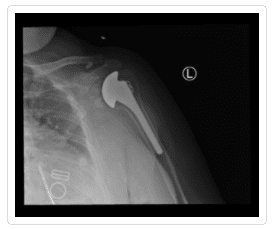

Total Shoulder Arthroplasty – A shoulder joint replacement surgery involves removing damaged bone and tissue and replacing them with artificial pieces or prosthesis. The procedure may involve only replacement of the head of the humerus bone or replacement of the entire ball and socket (glenoid) joint. The artificial components, made of metal or plastic, may be cemented into place or “press fit” into the socket if the bone is still in good condition.

Hemiarthroplasty – Also known as a partial replacement, a hemiarthroplasty involves replacing the humerus or arm bone with a prosthetic metal implant while the shoulder joint is left more or less intact. The shoulder osteoarthritis procedure may involve replacing the head of the humerus with a metal ball and stem as well as the arm bone or simply resurfacing the humerus head with a prosthesis that fits over the bone like a cap, preventing further wear and tear.